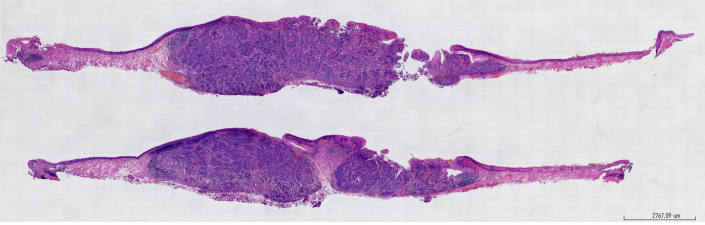

一、病理标本的制备

二、免疫组织化学的病理诊断及其在癌症治疗中的应用

免疫组织化学诊断-1:HE染色诊断为低分化癌的肺癌2例免疫组织化学诊断-2:根据雌激素受体(ER)、孕酮受体(PgR)和Her2蛋白的表达对癌症(导管腺癌)进行分类。免疫组织化学诊断-3:检查雌激素受体(ER)、孕酮受体(PgR)和Her2蛋白的表达对于选择合适的癌症治疗是必要的

数字病理促进了远程诊断网络,使病理学家能够远距离分析和诊断医疗状况。这在获得专业医疗专业人员的机会有限或及时诊断至关重要的情况下尤其有用。远程工作,特别是以远程病理学的形式,允许病理学家在家工作,同时对组织样本进行诊断评估。基于家庭的远程病理学可以提高效率,减少诊断的周转时间,并为病理学家提供灵活性,尤其是在现场工作可能具有挑战性或不可用的情况下。 2.免疫组化病理诊断及其在癌症治疗中的应用(1960~) 3.使用组织标本通过荧光原位杂交(FISH)检测基因改变(1980~) 4.使用组织标本的下一代DNA或RNA测序(2000s~)大会官网:www.avdc-china.com